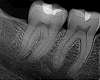

The NASA Imager Dentists Use DailyPasadena CA (JPL) Feb 28, 2017 When sitting in the dentist's chair, few patients think of NASA. But the space agency is there nonetheless, in the sensor that enables high-resolution, digital X-ray imagery that helps the dentist s ... more